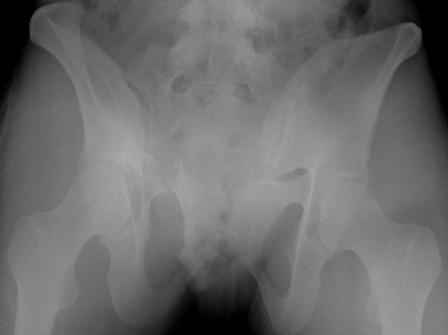

Серия до- и послеоперационных снимков этой пациентки. Хотя бы post factum обсудить. Не знаю, что можно сделать с задними отделами стержневым аппаратом, но три крепких парня открытым путем с помощью "волшебных" слов еле-еле смогли отрепонировать - сзади все было очень ригидно!

Здравствуйте, Евгений! У меня видна только дооперационная проекция inlet.

я бы остановился на передней раме, операция - 30 мин, в таком варианте вроде бы репозиция - ничего, но когда давать нагрузку, ведь в лонном сочленении тоже есть подвижность? а если не давать - зачем операция?

Уважаемые коллеги объясните не совсем понимаю как можно устранить и фиксировать вертикальное смешение таза с нарушением целостности заднего полукольца не понимаю к чему привязаться аппаратом для того чтобы удержать смещение я полагал что для этой цели необходима техника введения Транспедикулярного фиксатора да и на прямой проекции похоже линия перелома уходит в сустав выполнялась ли косая подвздошная косая запирательная проекции